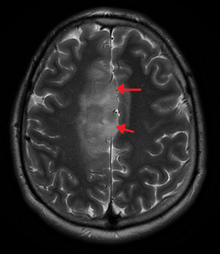

An X-ray computed tomography (CT) or magnetic resonance imaging (MRI) scan is necessary to characterize the anatomy of this tumor as to size, location, and its heter/homogeneity. However, final diagnosis of this tumor, like most tumors, relies on histopathologic examination (biopsy examination).

If resected, the surgeon will remove as much of this tumor as possible, without disturbing eloquent regions of the brain (speech/motor cortex) and other critical brain structure. Thereafter, treatment may include chemotherapy and radiation therapy of doses and types ranging based upon the patient's needs. Subsequent MRI examination are often necessary to monitor the resection cavity.